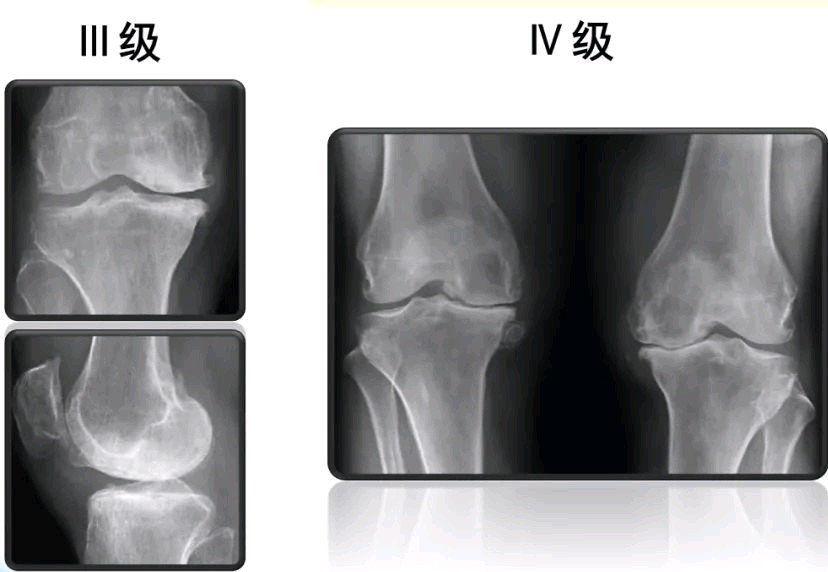

X线:膝关节退行性变。

膝骨关节炎是指膝关节表面软骨失去弹性,导致软骨下骨质受力增加,造成膝关节软骨磨损加速、变薄,使得骨硬化、变形、囊性变,出现关节间隙变窄,从而导致膝关节功能病废。

膝骨关节炎常见于中老年人群,临床尤其多见于绝经后女性,是一种以退行性病理改变为基础的疾患。膝骨关节炎典型的症状:单侧或双侧膝关节疼痛,初起时上下楼梯疼痛明显,坐起立行时膝部酸痛不适等,有一个很明显的症状就是膝关节发胀,这是因为人体都有自我保护的作用,膝关节软骨磨损时会出现滑膜充血分泌大量的滑膜液充盈膝关节腔;病情加重时会有膝关节局部肿胀、弹响、积液等,站久或行久时膝关节疼痛剧烈。如不及时治疗,慢慢出现膝关节软骨磨损硬化,周围骨质增生,膝关节软骨内神经损伤导致分泌关节液不足,最终会引起关节畸形、僵硬、残废。当然,在膝关节部位疾患,常见的还有膝关节滑膜炎、韧带损伤、半月板损伤、膝关节游离体、腘窝囊肿、髌骨软化、鹅足滑囊炎、膝内/外翻等关节疾病。所以,出现膝关节疼痛,建议尽早至医院骨科门诊就诊,经过检查,明确诊断,及时治疗。